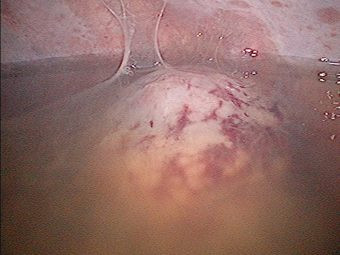

Derrame pleural derecho mas tumor de mediastino posterior